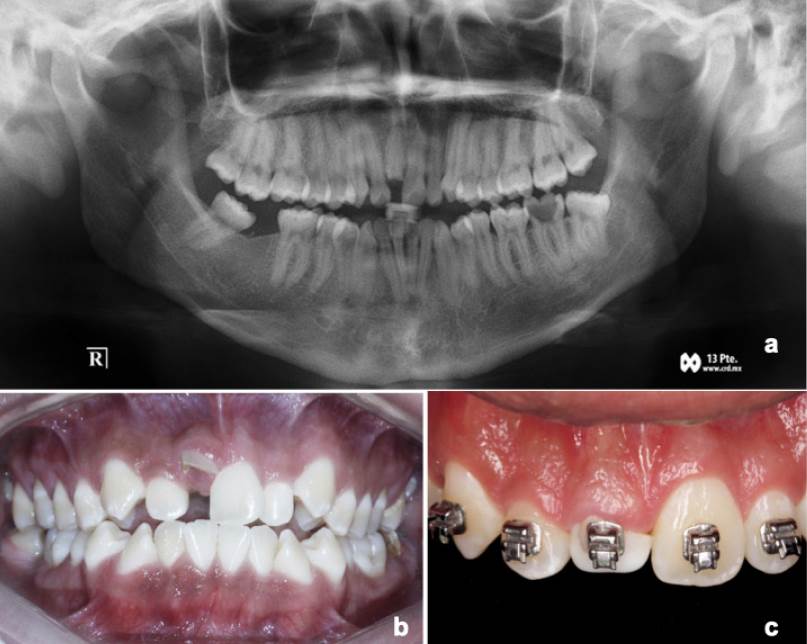

Paciente masculino de 21 años de edad que asistió a consulta dental para su rehabilitación. Durante el examen clínico intraoral se observó una buena higiene, sin presencia de lesiones sospechosas en mucosas. En el diente 11 se observó una fractura coronal no complicada, que se extendía por debajo del margen gingival, involucrando esmalte, dentina y cemento, de acuerdo con la guía de la Asociación Internacional de Traumatología Dental (IADT)8,9. Según lo expresado por el paciente durante el interrogatorio, la fractura es resultado de un accidente en bicicleta que tuvo a la edad de 11 años, así como fractura del diente 37 (no rehabilitable) y ausencia de diente 46 (Figura 1.A-B). Siguiendo la escala de severidad en rehabilitación descrita por Samet y Jotkowitz10, se estableció una Clase X para el diente 11, donde se valoraron la condición periodontal y soporte óseo alveolar, estructura dental sana remanente, condición endodóntica, plano oclusal y posición del diente. Al realizar interconsulta con periodoncia, ortodoncia y endodoncia se elaboró un plan de tratamiento integral, con la finalidad de mejorar el pronóstico en términos generales, pero sobre todo rehabilitar el diente 11 y alcanzar una Clase B acorde con Samet y Jotkowitz10.

Figura 1 Presentación del caso con finalización de tratamiento de ortodoncia. A. Radiografía inicial. B. Fotografía clínica inicial. C. Finalización del tratamiento de ortodoncia y colocación correcta del diente 11 en el arco dental.

Se inició el tratamiento con operatoria dental, retirando lesiones cariosas y obturando con resinas, para posteriormente canalizar a ortodoncia. Durante la fase de ortodoncia, se utilizaron brackets de autoligado pasivo con torque estándar, slot 0.22”. Se inició con arco Copper Ni-Ti 0.014”; para la segunda fase se utilizaron arcos Copper Ni-Ti 0.018” y 0.018” X 0.025”, y al final con arco TMA 0.019” x 0.025”. La elección de arcos se basó en las ventajas que presentan dichos arcos, como son fuerzas ligeras, continuas y controladas.